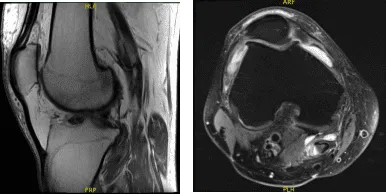

A 57-year-old patient was in our office with complaints regarding right knee pain. He tried physical therapy as well as anti- inflammatory medications, which did not help. He got an MRI done, which showed complex medial meniscus tear.

MRI Right Knee Non-contrast